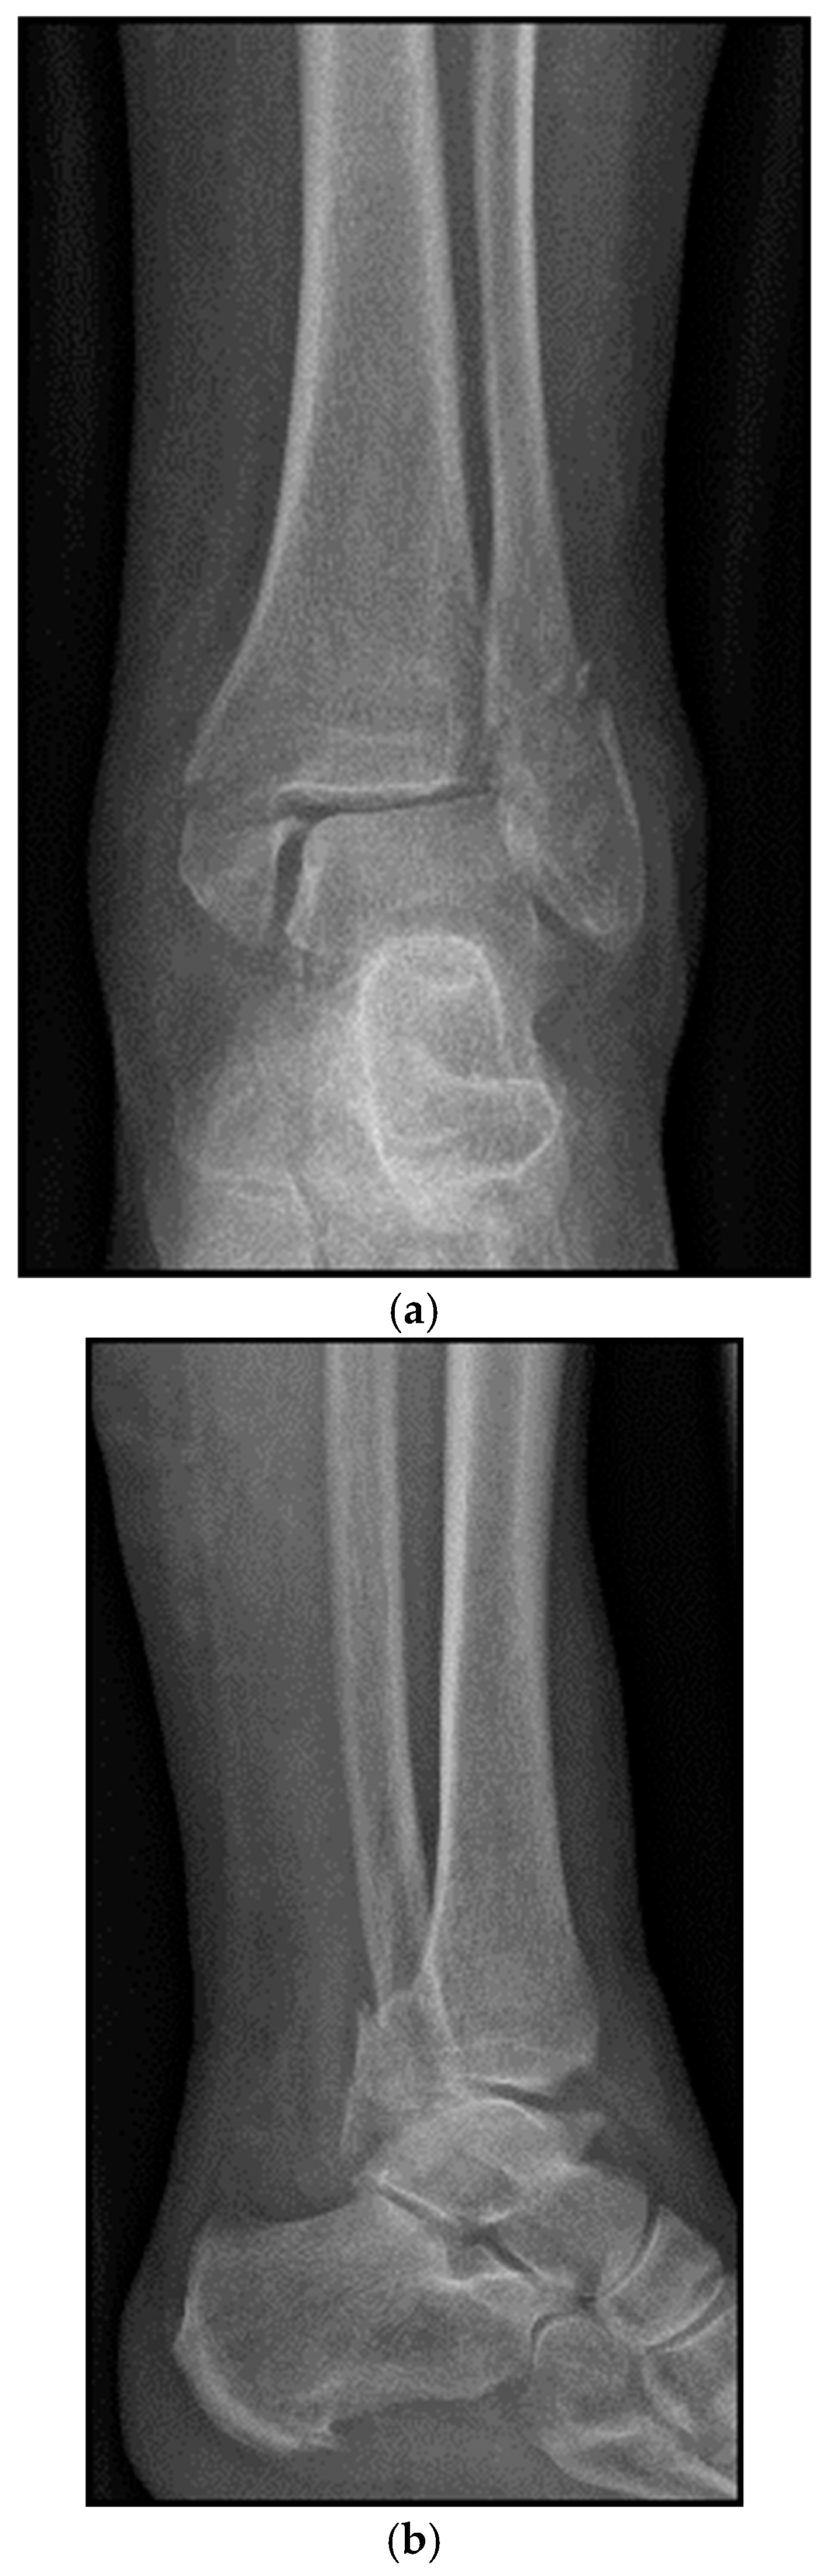

4. Classification

5. Case Description